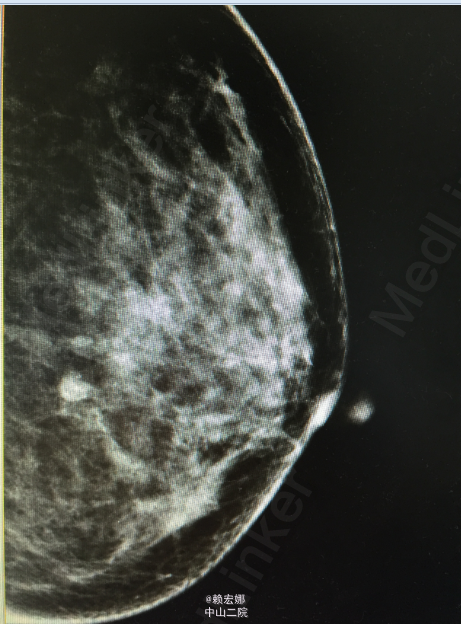

患者,女,31岁,发现左侧腋窝肿物1月

左侧腋窝可触及淋巴结肿大,大小约3cm,伴轻微疼痛感,双乳未触及明显肿物,无明显胸闷、乏力,无全身骨关节疼痛。外院B超:左侧乳腺实质性结节(增生结节可能,建议定期复查),左侧腋下低回声结节(考虑肿大淋巴结可能),建议进一步检查。我院B超:左乳实性低回声团,高度怀疑恶性病变(BI-RADS IVc类),建议住院手术。

患者术前检查未见明显禁忌症,局麻下行左乳肿物穿刺活检术,术后病理:(左腋下肿物)乳腺浸润性导管癌,II级,免疫组化:HER2(1+) ER (中至强+,80%)PR (-)Ki67(+,30%) P63(-) Calponin(-) E-cad (+)P53(+,10%)。患者乳腺癌诊断明确,遂在全麻下行左侧乳腺癌改良根治术,术后病理::1(左侧)乳腺浸润性导管癌,II级;2、乳头、四侧切缘和基底切缘未见癌浸润;3、(腋窝)淋巴结见癌转移(4/10),前哨淋巴结未见癌转移(0/2)。患者术后恢复良好,且未见明显化疗禁忌症,予以“表柔比星+紫杉醇脂质体”,化疗期间患者诉稍感恶习,无呕吐、乏力不适。